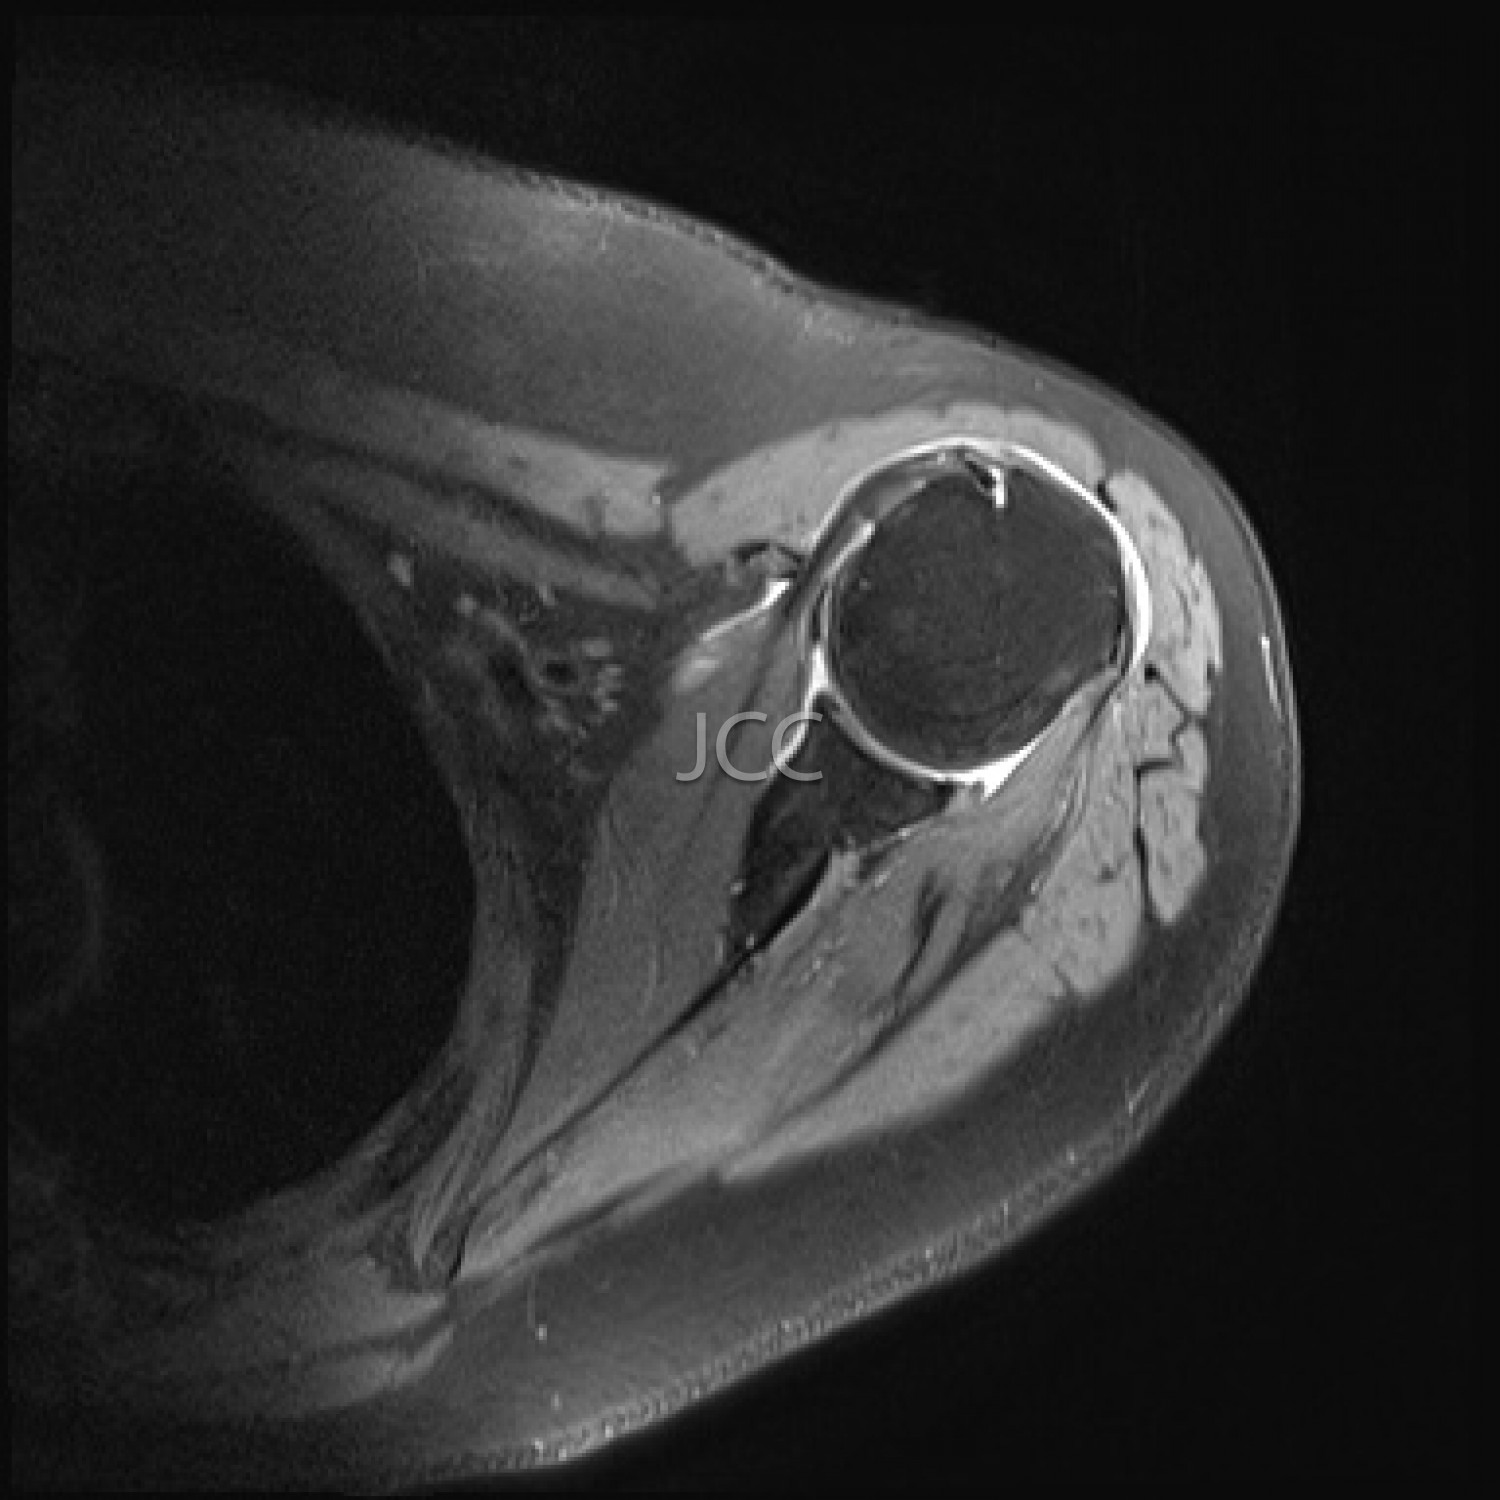

Ressonância Magnética de Alto Campo - RM Osteo-Articular

A Ressonância Magnética de Alto Campo é uma técnica de imagem que não utiliza radiação baseando-se num campo magnético e ondas de radiofrequência para estudar detalhadamente os órgãos do corpo humano.

Atualmente, com os equipamentos mais modernos de 1.5 e 3 TESLA é possível não só estudar cérebro, coluna e articulações constituindo, também, a técnica de eleição para avaliação vascular, coração, fígado e pâncreas.